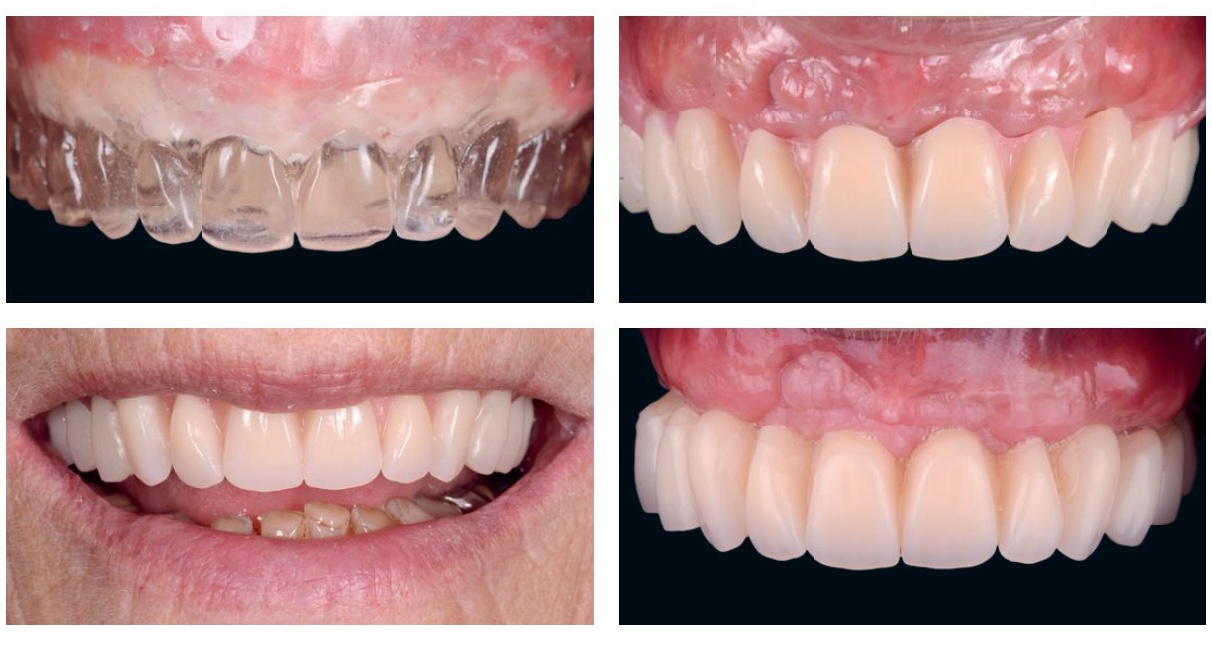

Photos cliniques illustrant des situations d'édentement complet et de passage à l'édentement

Dans les cas où l'espace prothétique est réduit et laisse présager une reconstitution sans fausse gencive, il est important de prêter une attention toute particulière à la position des dents par rapport à la crête : il est conseillé d'essayer le montage sans fausse gencive afin de prévisualiser au mieux l'esthétique finale. Cette précaution permet d'éviter les montages en porte-à-faux vis-à-vis de la gencive naturelle du patient. En effet, même en situation de faible résorption, la perte osseuse a fréquemment une composante horizontale et, dans une configuration sans fausse gencive, un compromis est nécessaire au niveau du montage pour donner l'illusion d'une situation de normalité.

Matérialisation du rapport crête-dents grâce à un duplicata transparent

Analyse du sourire et planification esthétique d'un cas de type FP1

Analyse du sourire et planification esthétique d'un cas de type FP2

Analyse du sourire et planification esthétique d'un cas de type FP3